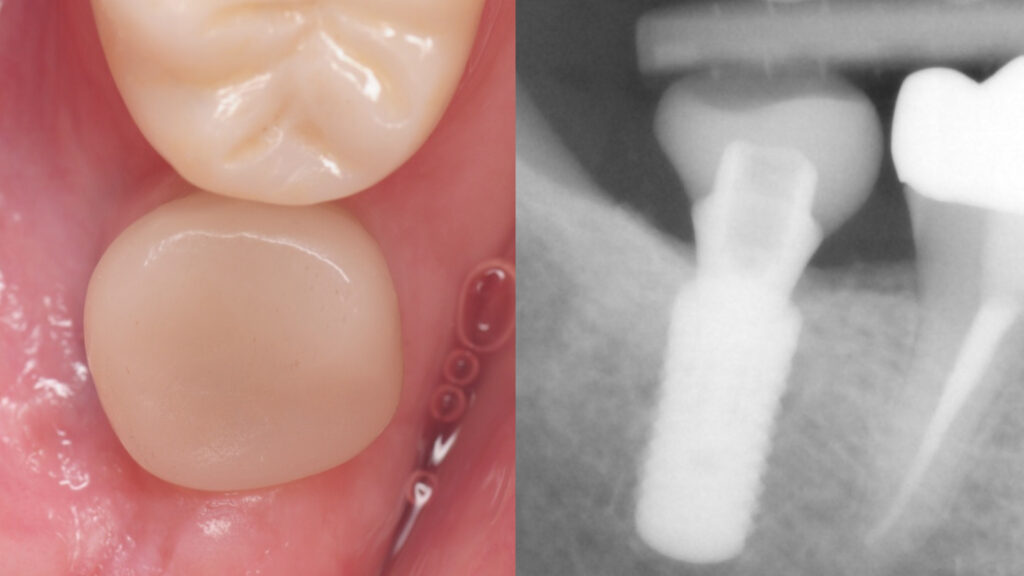

This patient complained of a ‘pressure’ sensation around the implant since its placement. The restoration was revised a couple of times with no change. Clinical and X-rays show a well-placed implant with completely healthy bone and gum tissue. Although the restoration appeared under-contoured, the implant had no specific problems. After two years, she finally asked her dentists to have the implant removed. Her dentists advised against it as they saw no issues with the implant. While such cases are sporadic, they present a debilitating situation for patients looking for a solution. The implant was ultimately removed in this patient and her symptoms resolved completely shortly after. The etiology remained unknown and we could not explain the precise reason for her improvement. We suspected poorly fitting abutment and restoration system or bite issues as possible causes. Revision therapy of the restoration was recommended but declined by patient who instead opted for its removal.